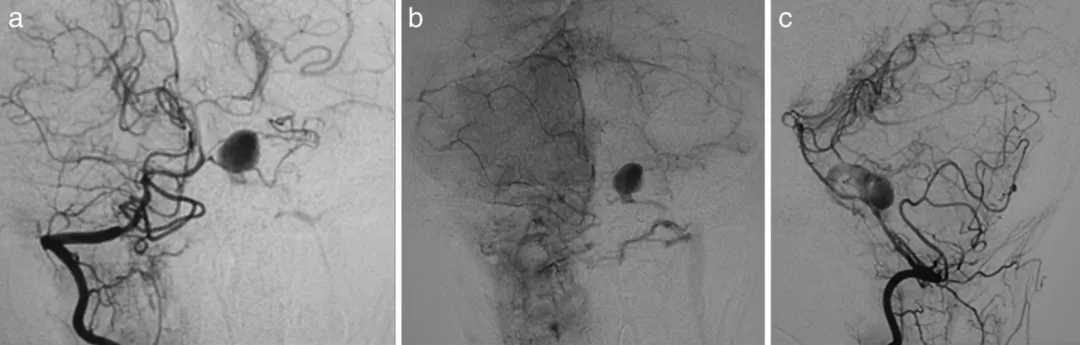

图a、b、c显示第7天右椎动脉造影,可见动脉瘤位于左小脑前下动脉近端

第14天复查造影显示动脉瘤明显增大,破裂风险显著增加

图d、e显示第14天右椎动脉造影,动脉瘤扩大,动静脉瘘更加明显